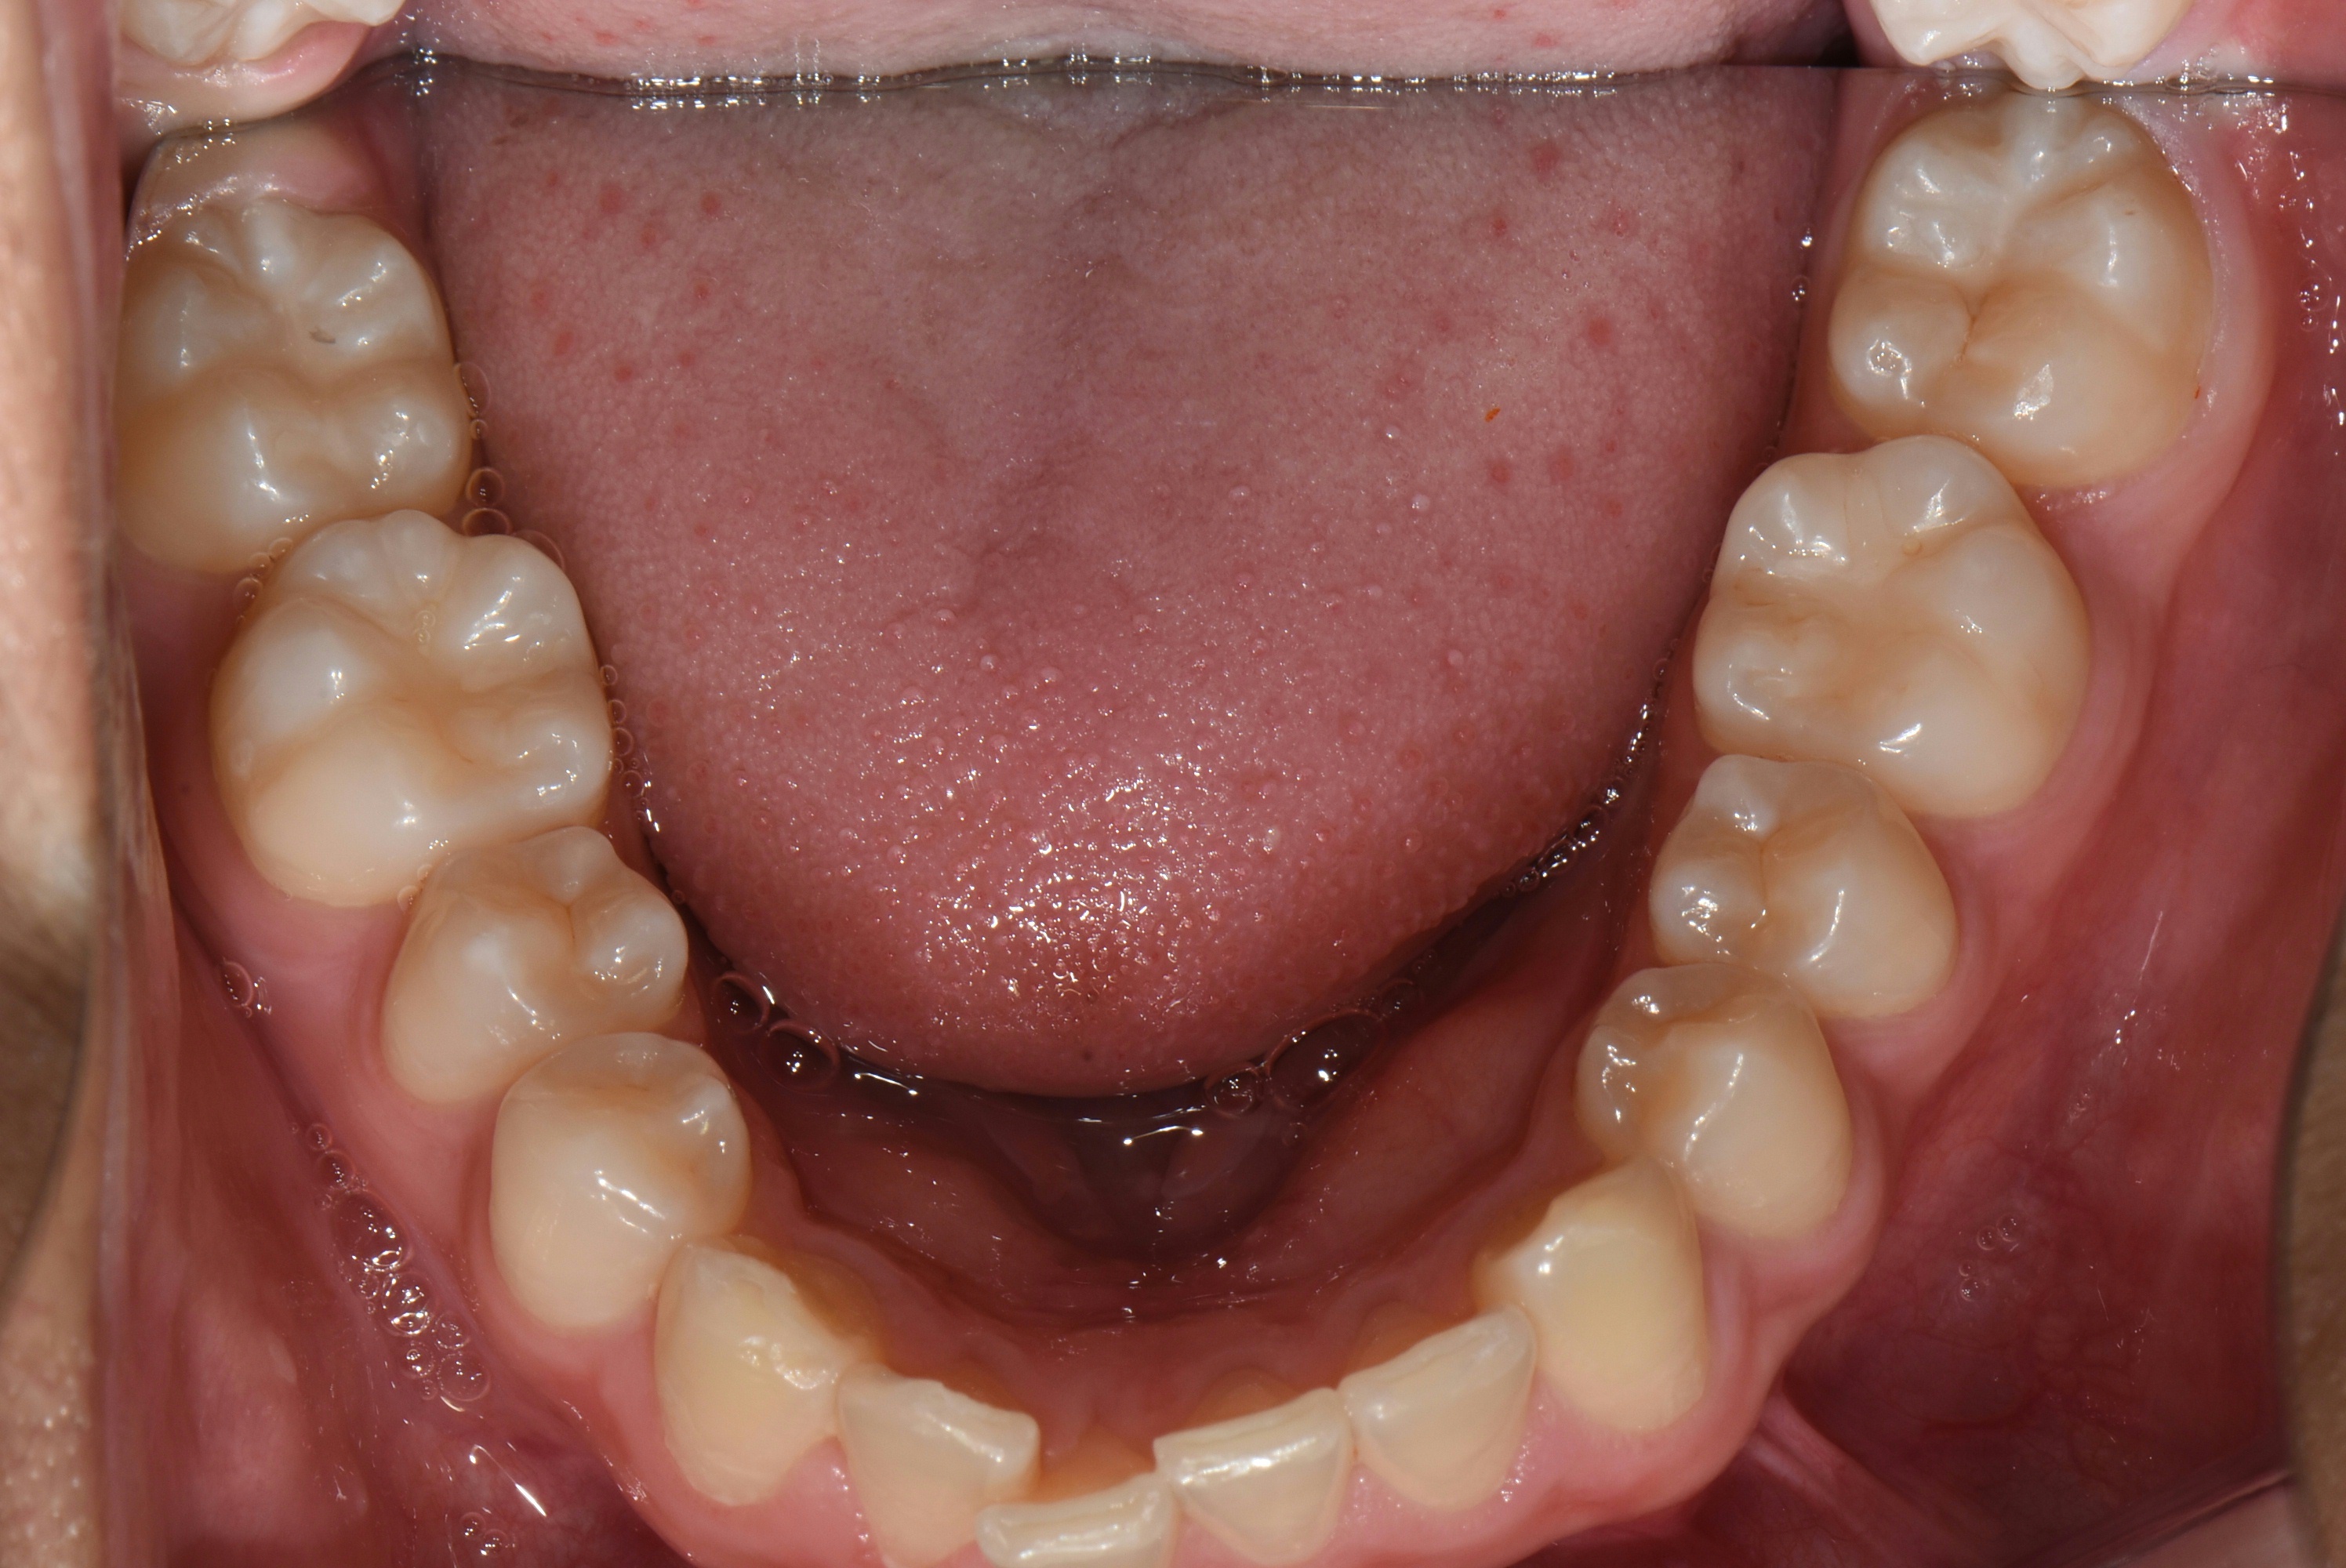

치료 전 사진입니다.